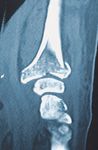

C1 Fraktur, Versorgung mit volarer Platte (breit) und Ulna-Hakenplatte

Präoperativ

Postoperativ

Klinischer Fall und CT-Aufnahmen mit freundlicher Unterstützung der

Klinik und Poliklinik für Unfall-, Hand- und Wiederherstellungschirurgie

Universitätsklinikum Gießen und Marburg GmbH